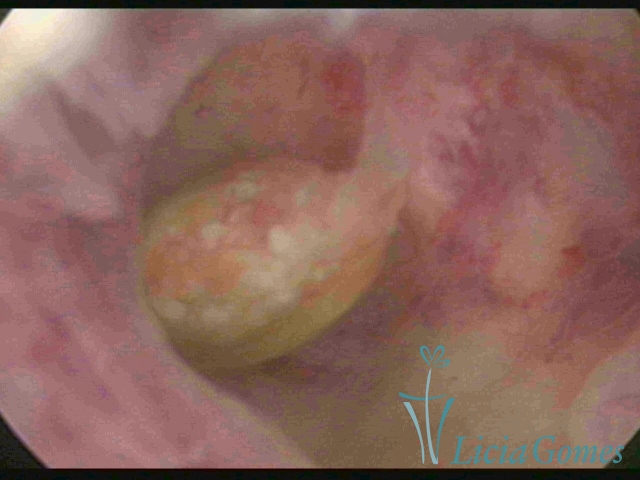

Dispositivo mirena e um mioma submucoso